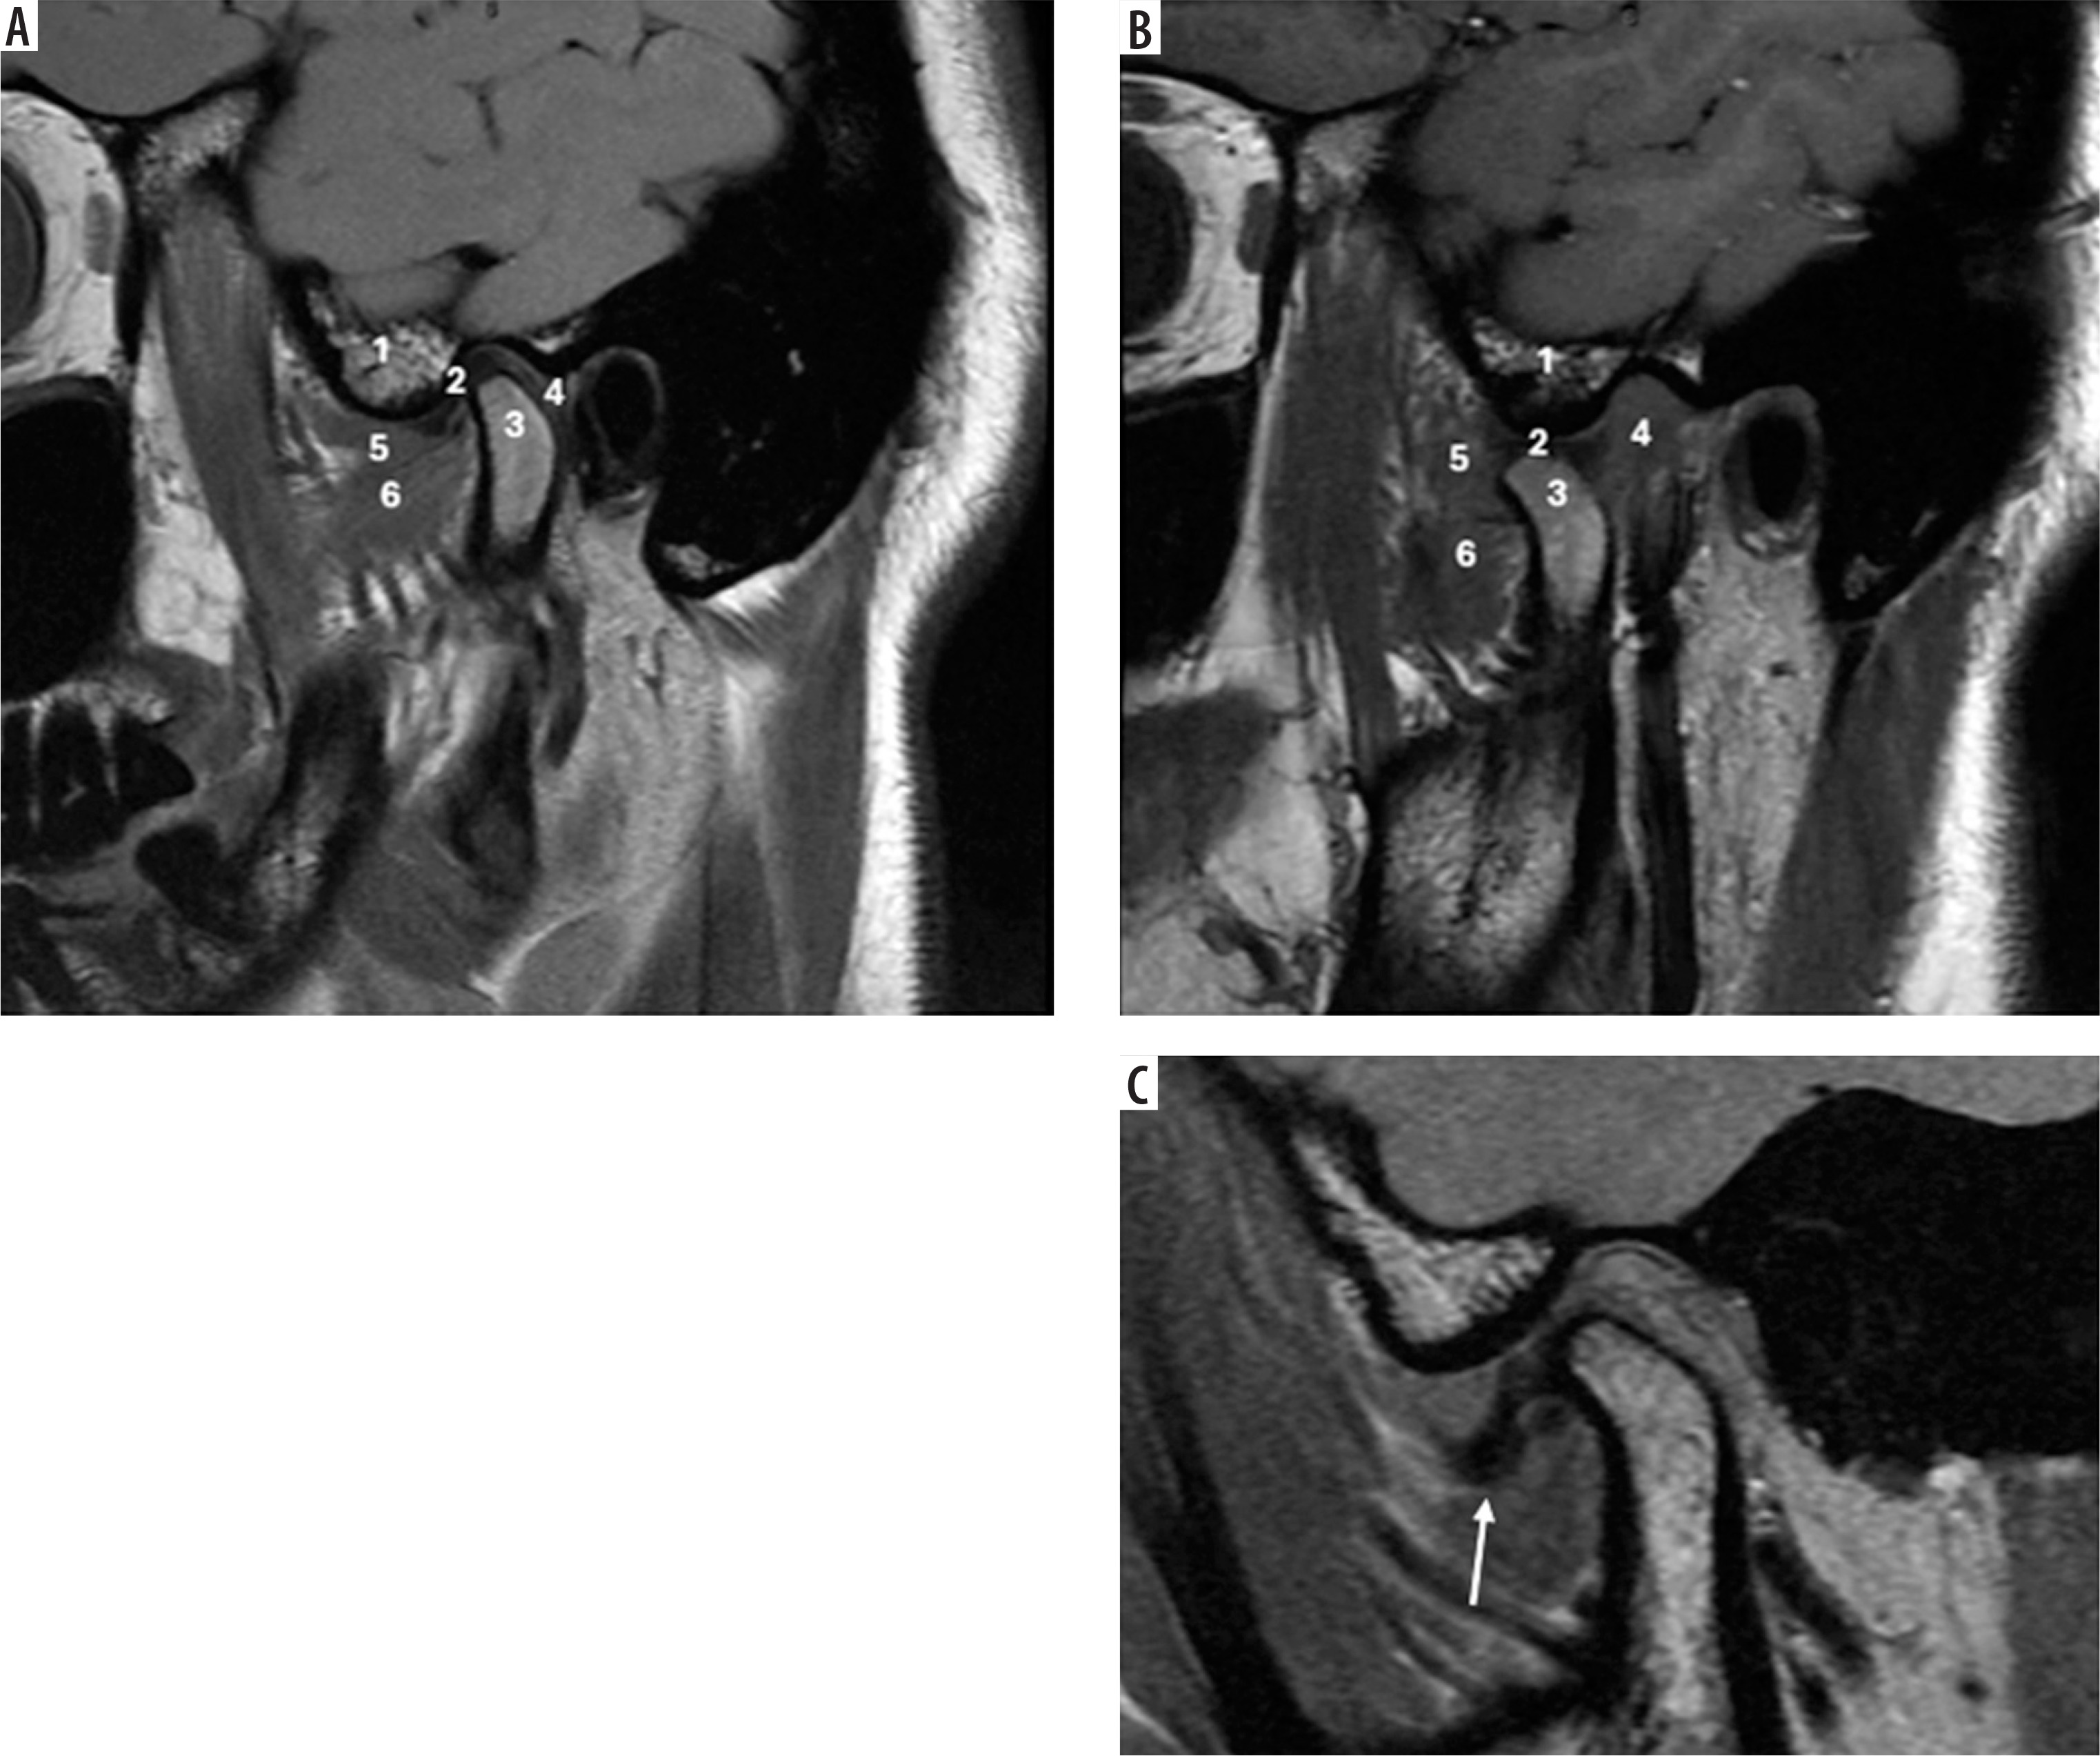

Case 5: Normal TMJ anatomy and disk displacement without reduction

On the MRI shown in Figure 8A, note that the cortex of the condyle is hypointense because there is no fluid or fat in the cortex. The same applied to the articular eminence and glenoid fossa, which show a hypointense outline. Also, note that within the articular eminence and condyle there are hyperintense signals because of fatty bone marrow contained within. The articular disk between the articular eminence and condyle is hypointense and shows a normal biconcave shape, and the posterior band of the disk end at the 12 o’clock position of the head of the condyle in close position (Figure 8A). In an open position, the articular disk is between the articular eminence and maintains a normal biconcave shape. Note the posterior flaring of the disk, and at least 50% of the disk is behind the contact point between the condylar head and articular eminence (Figures 8A-B). Assessing the disk and surrounding structures in TMJ dysfunction is the most important part for diagnosing internal derangement of TMJ in MRI, and the sagittal view is the most useful view for that [22]. The ability of MRI to produce precise images of the joint and surrounding structures without the use of ionising radiation, which is a possible concern associated with conventional imaging techniques such as X-rays and CT scans, is one of the main reasons for using MRI for the TMJ [22,23]. The MRI shown in Figure 8C in the open position shows the disk located anteriorly, which indicates a pathological condition of anterior disk displacement without reduction (Figure 8C).

Figure 8

Sagittal view of T1-weighted MRI images. A) Normal TMJ in closed position, B) normal TMJ in opened position C) anterior disk displacement without reduction. 1, articular eminence, 2, intermediate band of articular disk, 3, mandibular condyle, 4, retrodiscal tissue, 5 and 6 superior and inferior bellies of the lateral pterygoid muscle. Identifying internal derangements of the TMJ is crucial for accurate diagnosis and for planning both conservative and surgical interventions in TMJ disorders. [Figure 7A and 7B, Courtesy: Radiopaedia. DOI: https://doi.org/10.53347/rID-2748, rID: 2748; Figure 7C, Courtesy: Radiopaedia. DOI: https://doi.org/10.53347/rID-66812, rID: 66812]